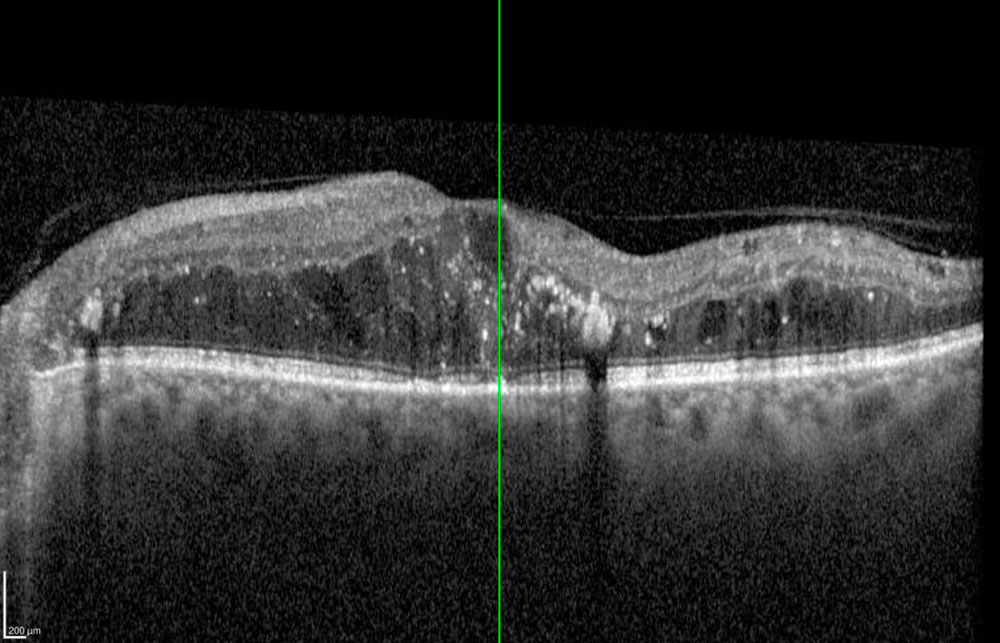

- OCT : évaluation de l’œdème maculaire.